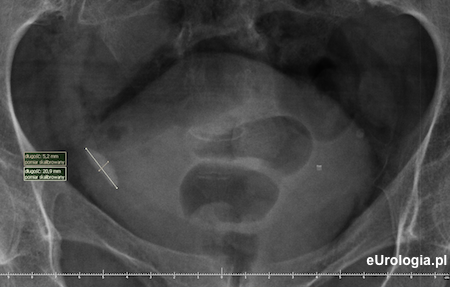

Zdjęcie przeglądowe nerek i pęcherza - cień wpaienny w miednicy po stronie prawej o wymiarach 20x10 mm

Zdjęcie wykonane godzinę po mikcji - zakontrastowany mocz w pęcherzu moczowym. Cień wapienny 20x10 mm będący złogiem w dolnym odcinku prawego moczowodu.

Kamień w dolnym odcinku prawego moczowodu - cień wapienny w miednicy małej widoczny na zdjęciu przeglądowym nerek i pęcherza.